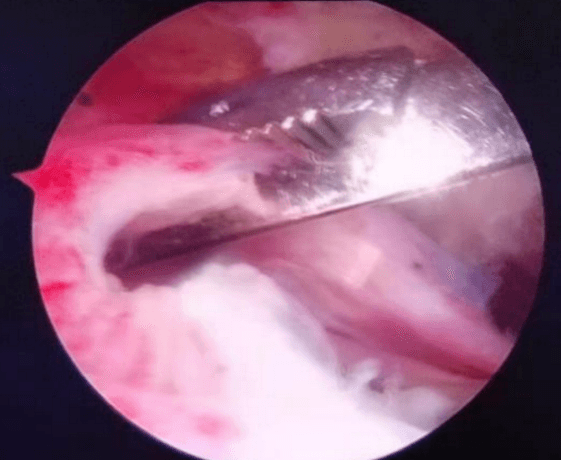

七年前從零出發(fā),從無(wú)到有,從有到精,李鵬主任帶領(lǐng)團(tuán)隊(duì)人員,先后在西安、上海、北京、廣州等獨(dú)家頂級(jí)關(guān)節(jié)運(yùn)動(dòng)醫(yī)學(xué)中心學(xué)習(xí),屢次開(kāi)創(chuàng)引進(jìn)新技術(shù),填補(bǔ)我院多項(xiàng)技術(shù)空白。先后開(kāi)展了首例膝關(guān)節(jié)鏡、首例肩關(guān)節(jié)鏡手術(shù),首例踝關(guān)節(jié)鏡手術(shù),首例肘關(guān)節(jié)鏡手術(shù),首例髖關(guān)節(jié)鏡手術(shù),完成了技術(shù)要求高、難度大的肩袖損傷修復(fù)手術(shù)、肩關(guān)節(jié)復(fù)發(fā)性脫位、BanKart損傷修復(fù)手術(shù),后交叉韌帶下止點(diǎn)骨折、膝關(guān)節(jié)多發(fā)韌帶損傷重建手術(shù)等,標(biāo)志著我院在骨關(guān)節(jié)運(yùn)動(dòng)醫(yī)學(xué)專(zhuān)業(yè)及關(guān)節(jié)鏡微創(chuàng)手術(shù)技術(shù)的顯著提升。

當(dāng)前越來(lái)越多的人意識(shí)到健康的身體是1,其他的都是0,有了這個(gè)1,其他的0才有了存在的意義和價(jià)值。所以越來(lái)越多的人開(kāi)始關(guān)注運(yùn)動(dòng)、開(kāi)始參與運(yùn)動(dòng)。然而,如何正確的運(yùn)動(dòng),如何預(yù)防運(yùn)動(dòng)損傷,如何在運(yùn)動(dòng)損傷后得到專(zhuān)業(yè)的治療,如何在運(yùn)動(dòng)損傷治療后得到快速的康復(fù)等,就需要一個(gè)專(zhuān)業(yè)的學(xué)科來(lái)解決這些問(wèn)題。這個(gè)學(xué)科就是運(yùn)動(dòng)醫(yī)學(xué)。運(yùn)動(dòng)醫(yī)學(xué)是一門(mén)新興的醫(yī)學(xué)科目,是醫(yī)學(xué)與關(guān)節(jié)運(yùn)動(dòng)相結(jié)合的綜合性應(yīng)用科學(xué)。主要是研究與關(guān)節(jié)運(yùn)動(dòng)有關(guān)的醫(yī)學(xué)問(wèn)題,包括關(guān)節(jié)的慢性勞損和急慢性損傷。范圍涵蓋了膝關(guān)節(jié)、肩關(guān)節(jié)、髖關(guān)節(jié)、踝關(guān)節(jié)及肘關(guān)節(jié)。膝關(guān)節(jié)骨關(guān)節(jié)炎、半月板損傷、交叉韌帶損傷、髕骨脫位、游離體(滑膜軟骨瘤?。?、肩關(guān)節(jié)凍結(jié)肩、肩袖損傷、肩峰撞擊征、肩關(guān)節(jié)復(fù)發(fā)性脫位、肩關(guān)節(jié)SLAP損傷、肘關(guān)節(jié)骨關(guān)節(jié)炎、踝關(guān)節(jié)撞擊癥、踝關(guān)節(jié)不穩(wěn)以及臀肌攣縮癥、髖股撞擊癥等,這些疾病都可以到運(yùn)動(dòng)醫(yī)學(xué)科就診。運(yùn)動(dòng)醫(yī)學(xué)能夠有效的、針對(duì)性的解決各類(lèi)急慢性關(guān)節(jié)疼痛。主要是利用關(guān)節(jié)鏡微創(chuàng)技術(shù),能夠快速有效的緩解關(guān)節(jié)疼痛,具有創(chuàng)傷小、恢復(fù)快、效果顯著等優(yōu)點(diǎn)。

微創(chuàng)、精準(zhǔn)、快速康復(fù)已成為骨科疾病與創(chuàng)傷治療的必然趨勢(shì)。我院骨關(guān)節(jié)及運(yùn)動(dòng)醫(yī)學(xué)亞專(zhuān)科是我院外科病院重點(diǎn)發(fā)展的亞專(zhuān)科方向。李鵬作為專(zhuān)業(yè)團(tuán)隊(duì)的負(fù)責(zé)人,科室目前配備有全套進(jìn)口關(guān)節(jié)鏡手術(shù)設(shè)備,高清顯像系統(tǒng),全體醫(yī)護(hù)團(tuán)結(jié)協(xié)作,嚴(yán)謹(jǐn)細(xì)致,踏實(shí)前行,以精湛的醫(yī)療技術(shù)和優(yōu)質(zhì)的護(hù)理服務(wù),為患者提供了優(yōu)質(zhì)醫(yī)療服務(wù),贏(yíng)得了廣大患者的信任和肯定。

髕骨脫位手術(shù)

肩袖損傷手術(shù)